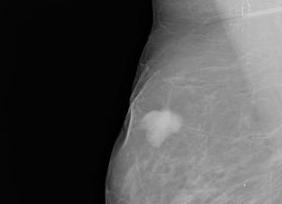

На маммограмме: в правой половине груди в центральном верхнем отделе узел 4,5х5,0х5.7 см с признаками злокачественного роста и лимфангоитом, достигающим кожи и грудной стенки и инфильтрирующий кожу на всем протяжении. В левой молочной железе — фиброаденоматоз.

Ультразвуковое исследование (УЗИ) от 26.04.2000 показало умеренно выраженные явления фиброза в левой молочной железе, в правой на границе верхних квадрантов определялось гипоэхогенное неправильной формы образование 4,5х4,7х5,4 см с признаками инфильтративного роста. Кожа отечная.